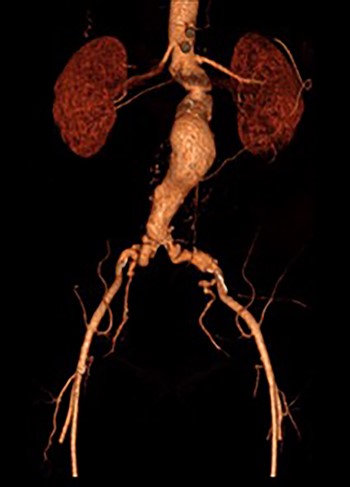

Post-EVAR angiogram showing acute thrombosis of the right limb and subtotal thrombosis of the left limb and trunk.

An angiogram at this stage demonstrated acute thrombosis of the right limb, and subtotal thrombosis of the left limb (Fig. 2). A further bolus of 2000 units Heparin was given intravenously. Thrombectomy was performed by advancing the 16Fr Sentrant sheaths into the limbs of the endograft followed by retraction under negative pressure. This manoeuvre restored antegrade arterial flow on both sides although there was a large volume of acute thrombus within the limbs of the endograft. A decision was made to perform intra-arterial thrombolysis. The 16Fr Sentrant sheath was removed from the left common femoral artery and haemostasis secured with the Proglides. The right-sided 16Fr sheath was downsized to 8 Fr sheath (the Proglide sutures were tightened around this sheath, achieving haemostasis around the smaller sheath). A multi-side hole straight angiographic catheter was placed in the body of the endograft for the thrombolysis. A bolus of 5 mg Actilyse (Boehringer Ingelheim, Ingelheim am Rhein, Germany) was given through this followed by a 1 mg/h infusion. An IV heparin infusion was started at 1000 units/h through the side arm of the 8 Fr sheath.